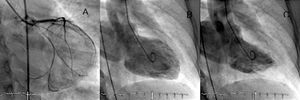

Reingresó por un episodio de dolor torácico en reposo y disnea. Se auscultaba un cuarto tono, un soplo sistólico en borde esternal izquierdo y crepitantes en ambas bases pulmonares. El ECG durante el dolor mostraba lesión subendocárdica inferolateral. Fue tratada con triple antiagregación y se realizó cateterismo de forma programada a las 24 h. Inmediatamente antes, la paciente presentó angina, disnea y saturación arterial del 86%, con crepitantes pulmonares. La coronariografía mostró una reestenosis difusa en el stent, con oclusión subtotal de la circunfleja proximal. La FEVI estaba ligeramente deprimida, con acinesia posterobasal y diafragmática. Tenía una insuficiencia mitral severa, que opacificó por completo la aurícula izquierda en el primer latido (fig. 1). Se realizó nueva angioplastia y se implantó con éxito un stent farmacoactivo. Tras la reperfusión se observó mejoría clínica, con desaparición del dolor y la disnea. Una nueva ventriculografía demostró la desaparición de la insuficiencia mitral (fig. 2). En el ecocardiograma realizado antes del alta, la FEVI era normal, sin alteraciones segmentarias, y se observó insuficiencia mitral leve.

Fig. 1. Coronariografía que muestra oclusión subtotal de la circunfleja proximal. Ventriculografía en diástole (A) y en sístole (B) con la aurícula izquierda totalmente opaca en relación con insuficiencia mitral severa.

Fig. 2. Coronariografía que muestra arteria circunfleja proximal tras la implantación del stent. Ventriculografía en diástole (A) y en sístole (B) con ausencia de insuficiencia mitral.